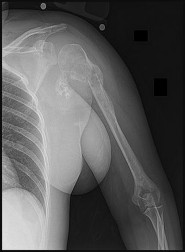

This patient has a dedifferentiated liposarcoma within a preexisting atypical lipomatous tumor. The imaging demonstrates a large fatty mass with increased internal septations proximally (the atypical lipomatous tumor) and a solid enhancing mass distally (the dedifferentiated portion). A biopsy reveals a high-grade liposarcoma. The other diagnostic responses do not reflect sarcomatous transformation of the lesion.

Surgical treatment of a high-grade sarcoma involves wide surgical resection. Radiation decreases local recurrence but does not clearly influence overall survival. The role of chemotherapy in high-grade soft-tissue sarcomas remains investigational; there is a modest (8%-15%) associated improvement in overall survival.

Intramuscular lipomas and atypical lipomatous tumors are treated with marginal resection alone. Radiation therapy for soft-tissue sarcomas may be given before or after surgery. When administered before surgery, patients have a higher wound complication rate but better long-term function attributable to lower rates of lymphedema, fibrosis, and contractures.